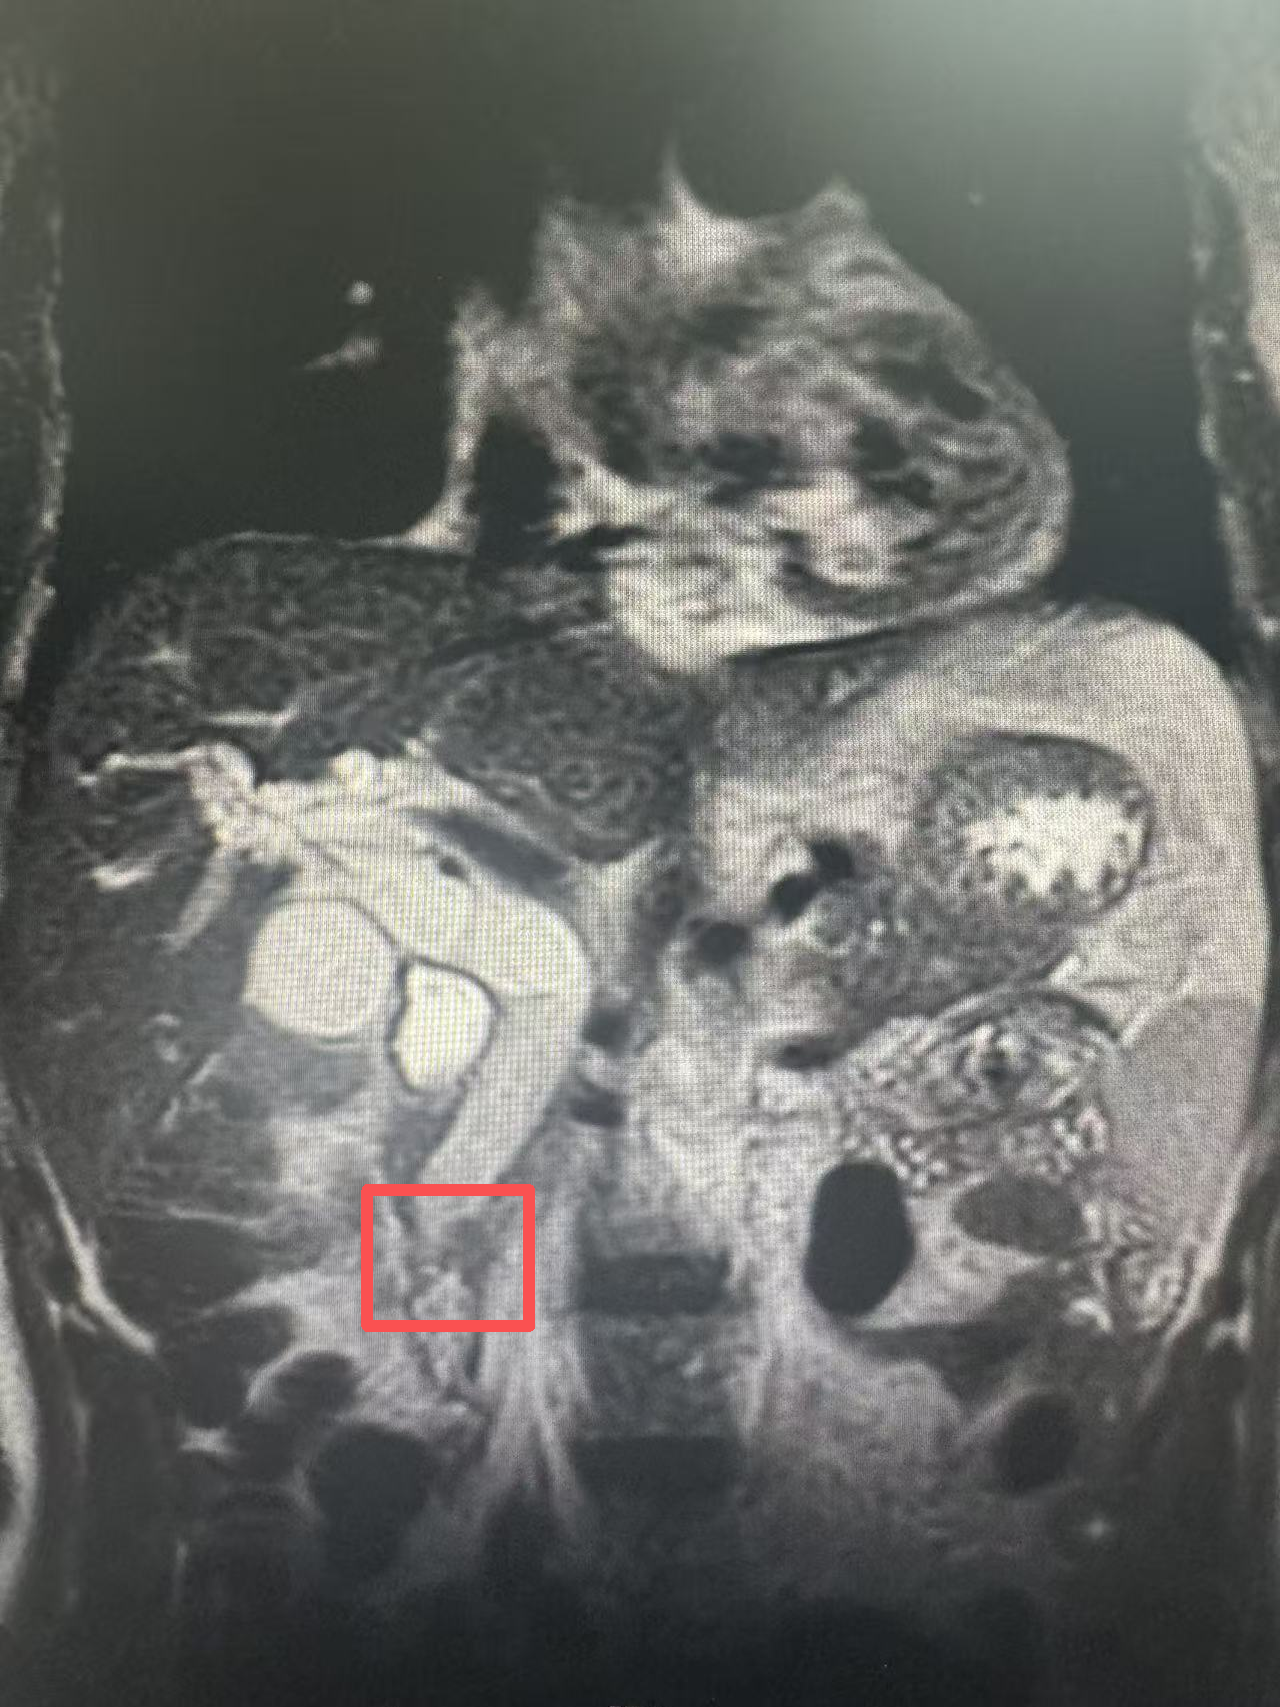

生化检验及影像学检查(增强CT及磁共振)结果证实了专家的担忧:患者总胆红素高达426.8umol/L,超过正常值20倍以上,肝脏功能已严重受损。同时,患者肝内外胆管严重扩张,胆总管下段梗阻,高度怀疑壶腹部占位性病变。

△标红处为肿瘤占位